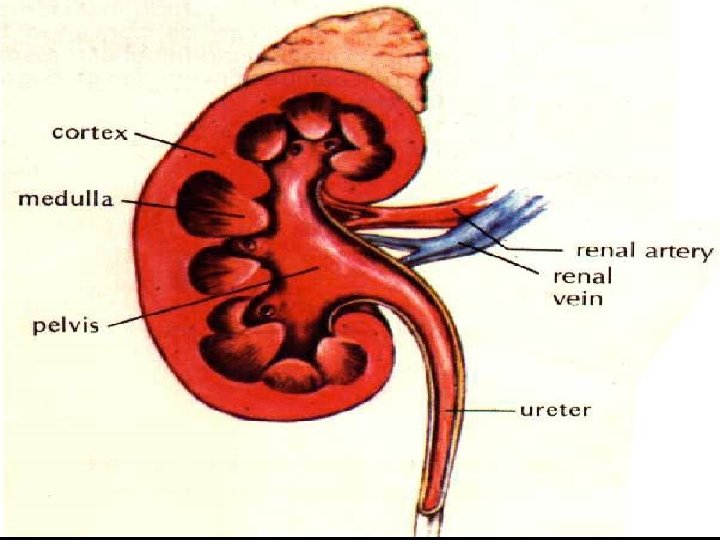

KIDNEY • Kidneys are bean shaped organs that filtere 180 lt. blood in a day. • Blood is come into kidney by renal artery. • Filtered blood leaves from kidney by renal vein.

STRUCTURE OF KIDNEY 1. Cortex: It contains glomerulus and Bowman’s capsules. 2. Renal Capsule: It surrounds and protects the kidneys.

3. Medulla: It is located under the cortex and has malphigian pyramids. Malphigian pyramids contains urine collecting canal and loop of henle. 4. Pelvis: It is innermost part of kidney. The urine is collected in pelvis.